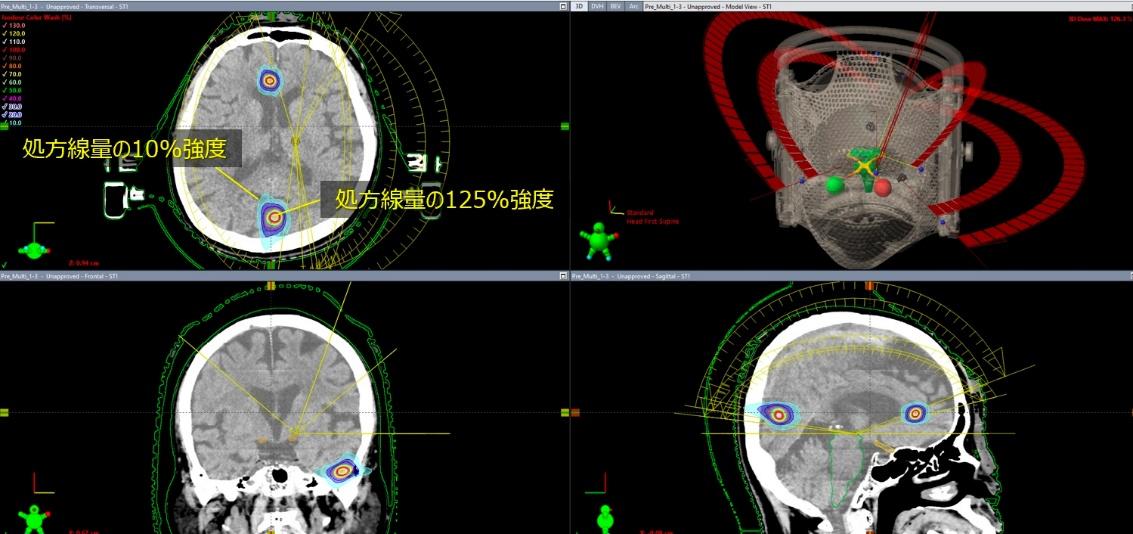

Elements Multiple Brain Mets SRS は、複数の脳転移に対する定位放射線治療(SRS)の治療計画を効率的に作成するためのソフトウェアです。脳内に複数存在する転移性腫瘍に対して、それぞれの病変を正確に捉えながら放射線を集中させる治療計画を、自動化・最適化することができます。

本ソフトウェアでは、MRIやCT画像をもとに病変の位置や形状を解析し、複数の腫瘍に対して同時に高精度な照射計画を作成することが可能です。これにより、腫瘍には十分な線量を届けながら、周囲の正常脳組織への影響を可能な限り抑えた治療を目指します。

また、治療計画作成の効率化により、患者さんの治療準備にかかる時間の短縮にもつながります。このように、Elements Multiple Brain Mets SRS は、複数の脳転移に対して安全性と精度の高い定位放射線治療を実施するための治療計画支援システムです。